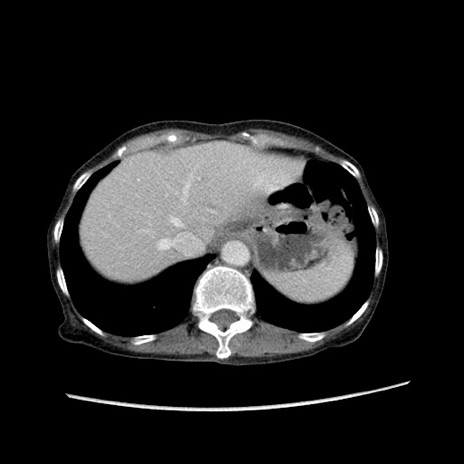

症例25(横断像)

【症例】80歳代女性

【主訴】胸のつかえ感

【現病歴】約9時間前に食後から胸のつかえた感じあり、嘔吐あり、来院。

【既往歴】胃癌(全摘)、胆摘、虫垂炎

【身体所見】心窩部に圧痛あり、反跳痛なし。

【データ】WBC 5700、CRP 0.05